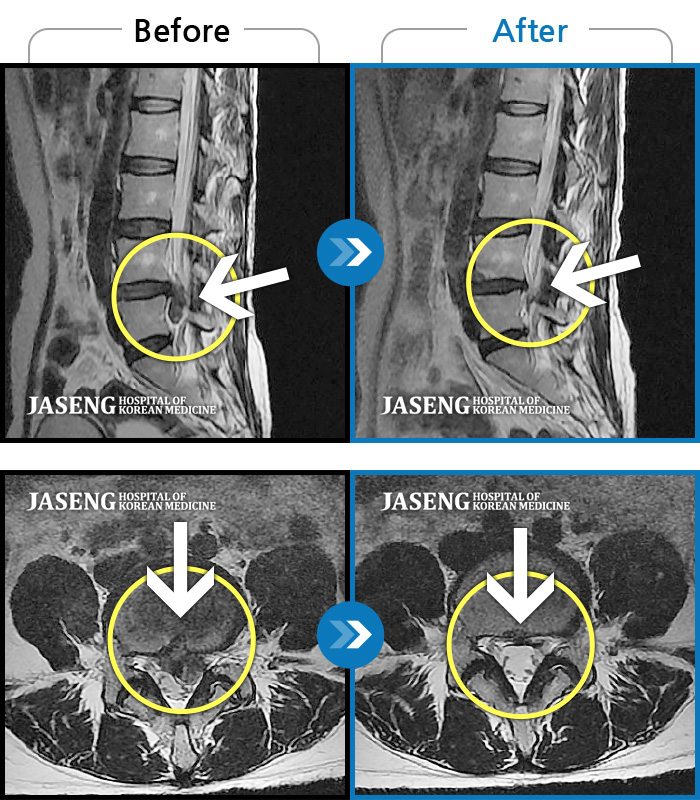

ȯںп Ǹ ǿ ԿǾ, ο ġ ۿ Ƿ ġḦ Ͻñ ٶϴ.